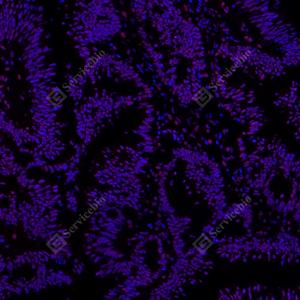

IF检测RING1蛋白(货号 GB112531)(红色). 样品: 小鼠胰腺, 4%多聚甲醛 (货号G1101) 固定12-24小时. 抗原修复: Tris-EDTA抗原修复液(pH 9.0) (G1203), 98℃, 20分钟. 封闭: 3% BSA(货号GC305010)的PBS溶液, 室温孵育30分钟. —抗: 1: 800稀释, 4℃ 孵育过夜. 二抗: Cy3标记山羊抗兔IgG (H+L) (货号GB21303), 1: 300稀释, 室温孵育1小时. |